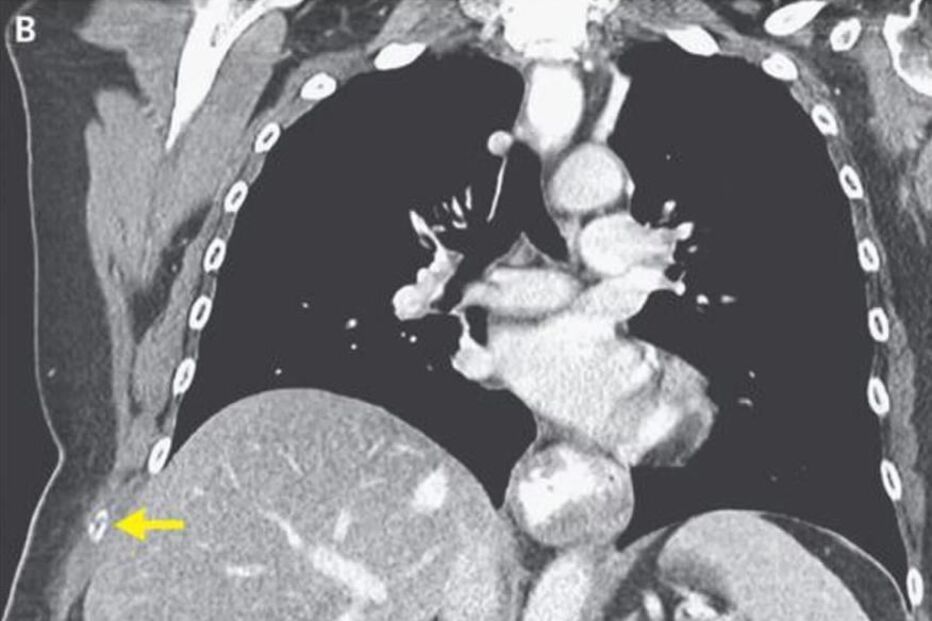

Uma mulher de 66 anos partiu a costela do lado direito após duas semanas intensas de tosse seca, resultantes de uma gripe que tinha contraído, em Massachussetts, nos EUA.

A utente, que tinha sido diagnostica com gripe uns dias antes, dirigiu-se ao hospital com muitas dores. Foi aí que o médico se apercebeu que tinha um enorme hematoma por baixo do peito direito e uma dor aguda sempre que se lhe tocava.

Um exame revelou que a norte-americana tinha uma fratura nas costelas e ainda uma hérnia na parede do tórax.

A equipa médica acredita que a fratura terá sido causada pela tosse forte que a mulher sofreu nos últimos dias. A norte-americana de 66 anos acabou por ser operada e foi recomendada a tomar um antibiótico mais forte para curar a gripe e a tosse.